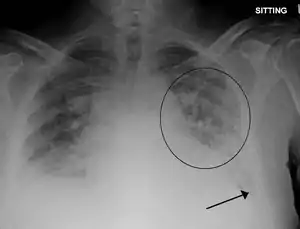

Low oxygen saturation and disturbed arterial blood gas readings support the proposed diagnosis by suggesting a pulmonary shunt. A chest X-ray will show fluid in the alveolar walls, Kerley B lines, increased vascular shadowing in a classical batwing peri-hilum pattern, upper lobe diversion (increased blood flow to the superior parts of the lung), and possibly pleural effusions. In contrast, patchy alveolar infiltrates are more typically associated with noncardiogenic edema[2]